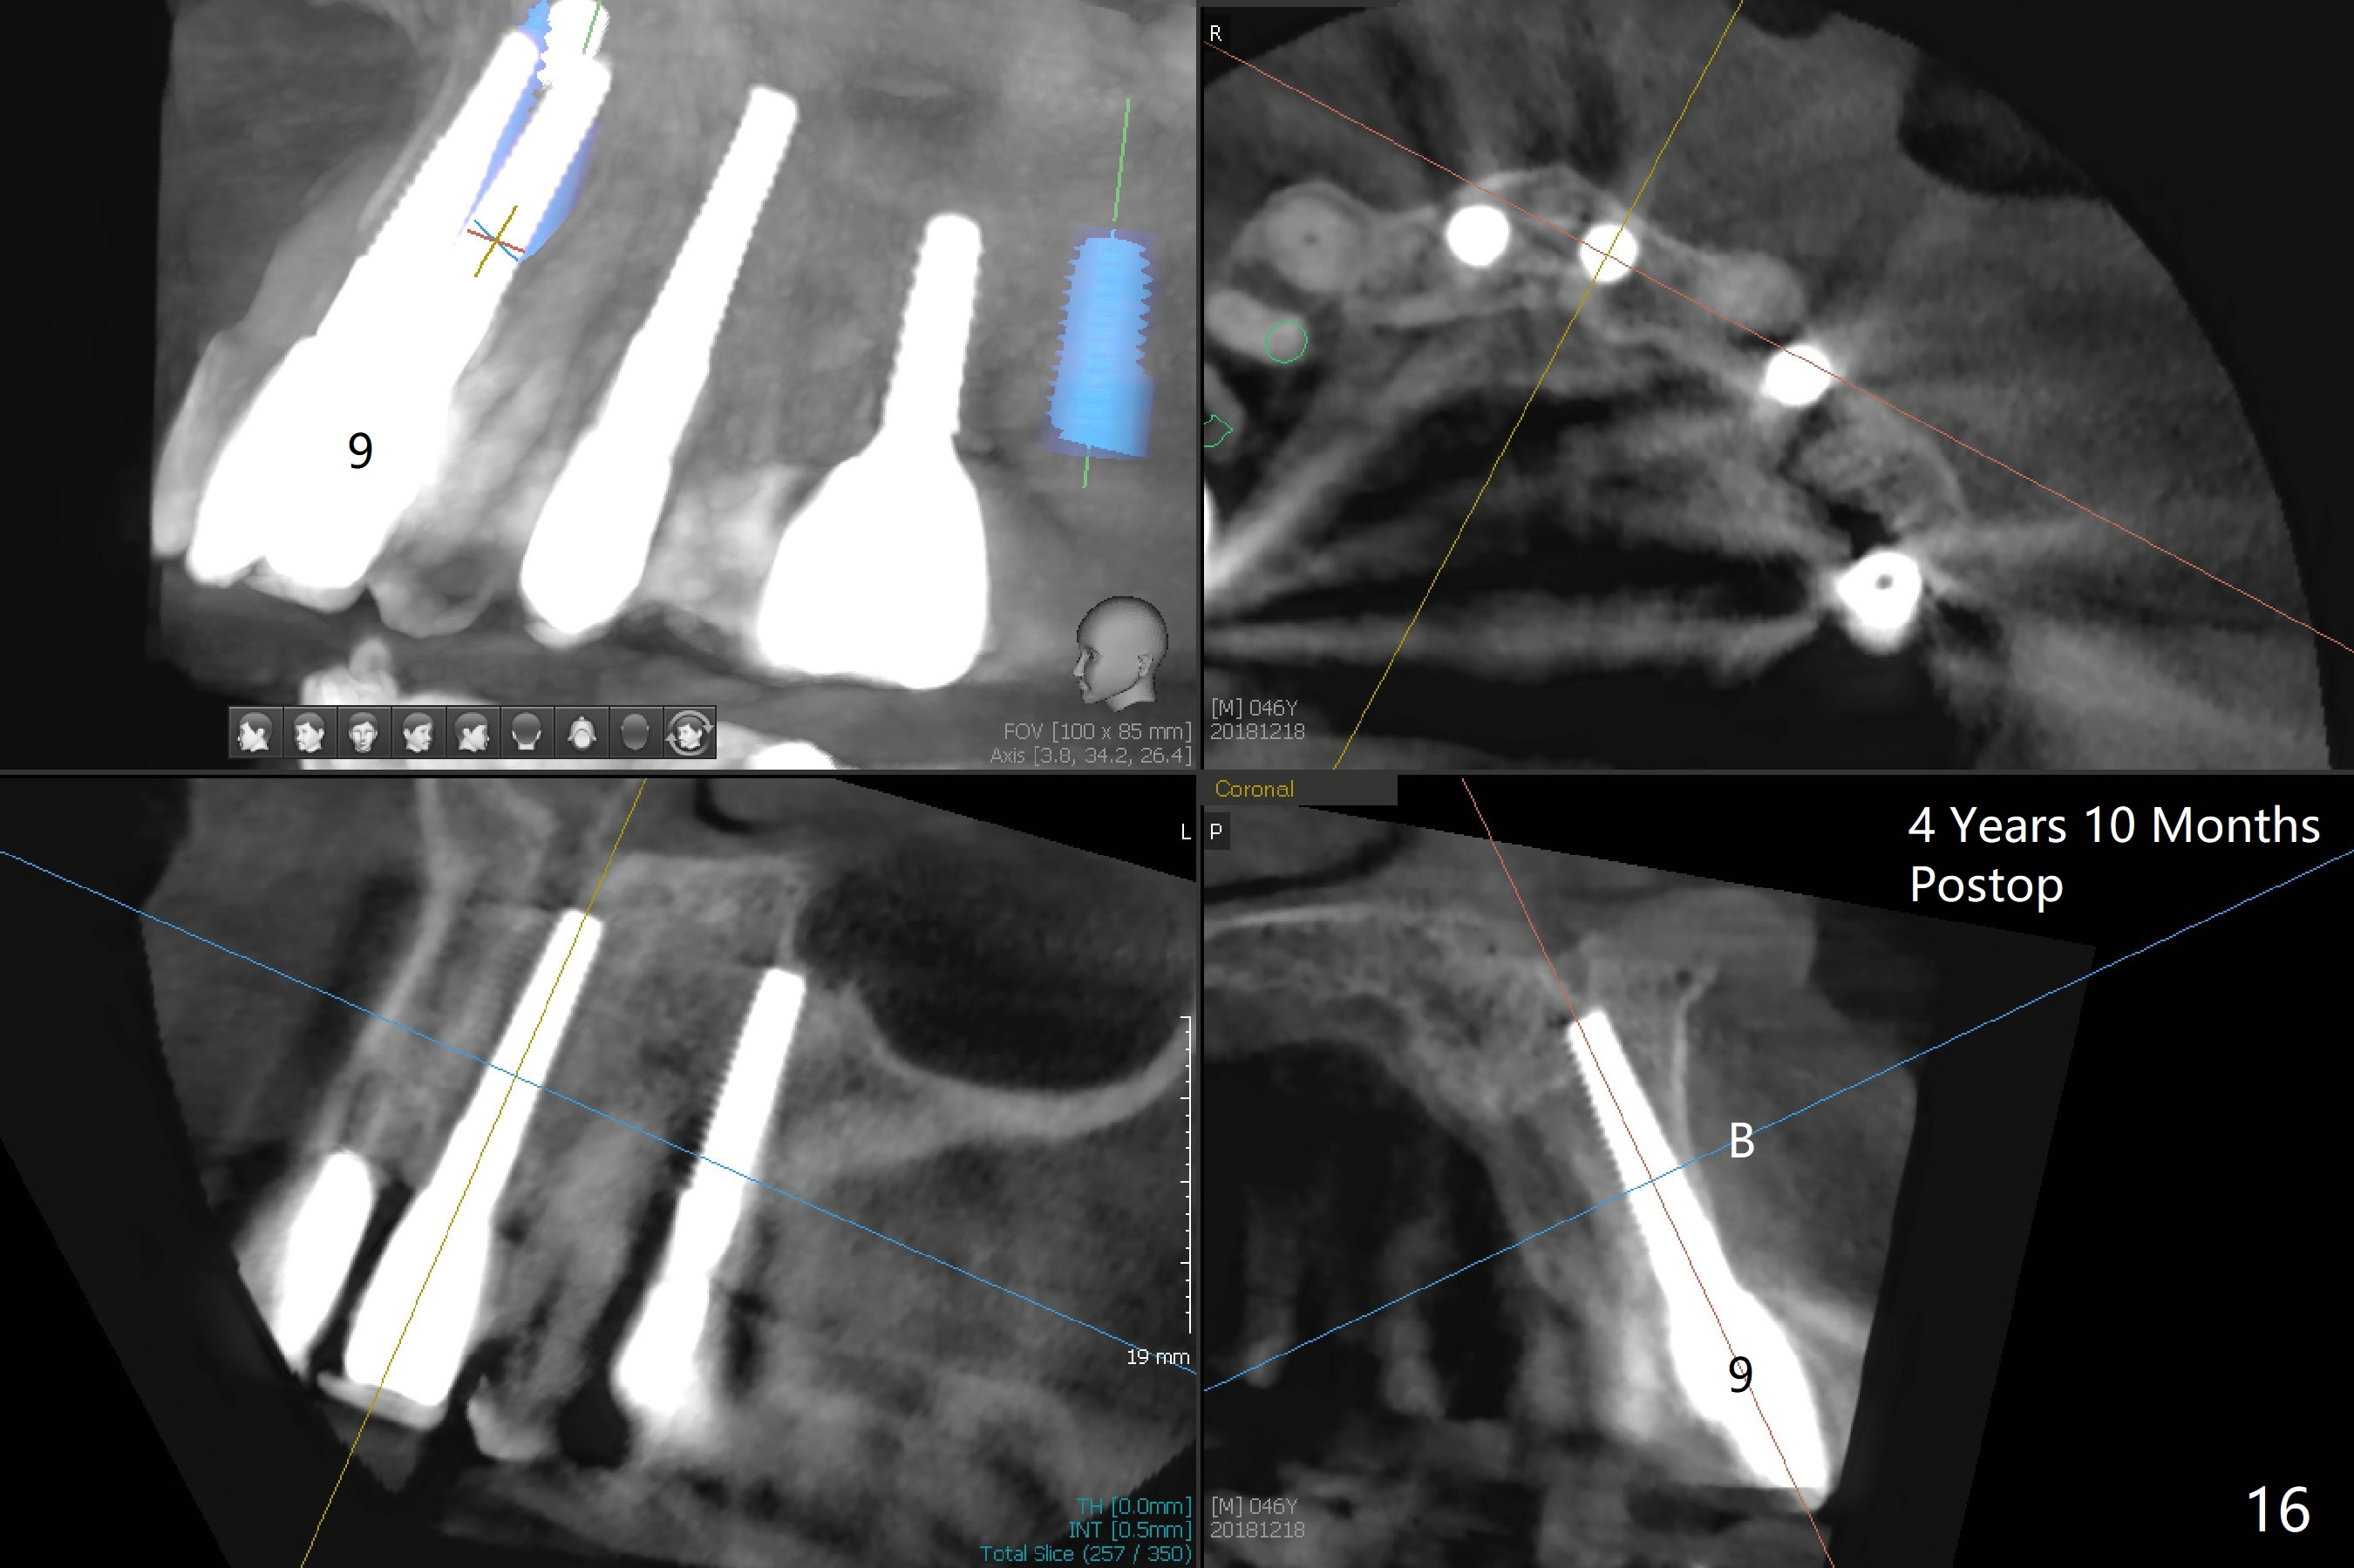

These two anterior implants remain stable 2 months 20 days postop, since one of the immediate provisionals has incisal chip (Fig.11 *) while both of them are splinted (<) to increase retention. There is no complain about paresthesia around the incisal papilla due to separation of the nasopalatine nerve. Mesiodens sockets disappear 7 months postop (Fig.13). There is no bone loss 2 years 9 months postop (Fig.14 panoramus) or 4 years 10 months postop (Fig.15,16 CT). The buccal gingiva is reddish and swollen with bleed on probing and history of pain 7 years post cementation (Fig.17). There is no bone loss in PA (Fig.18). The buccal plate at #9 is thinner than that at #8 4 years 10 months post cementation (Fig.19,20).